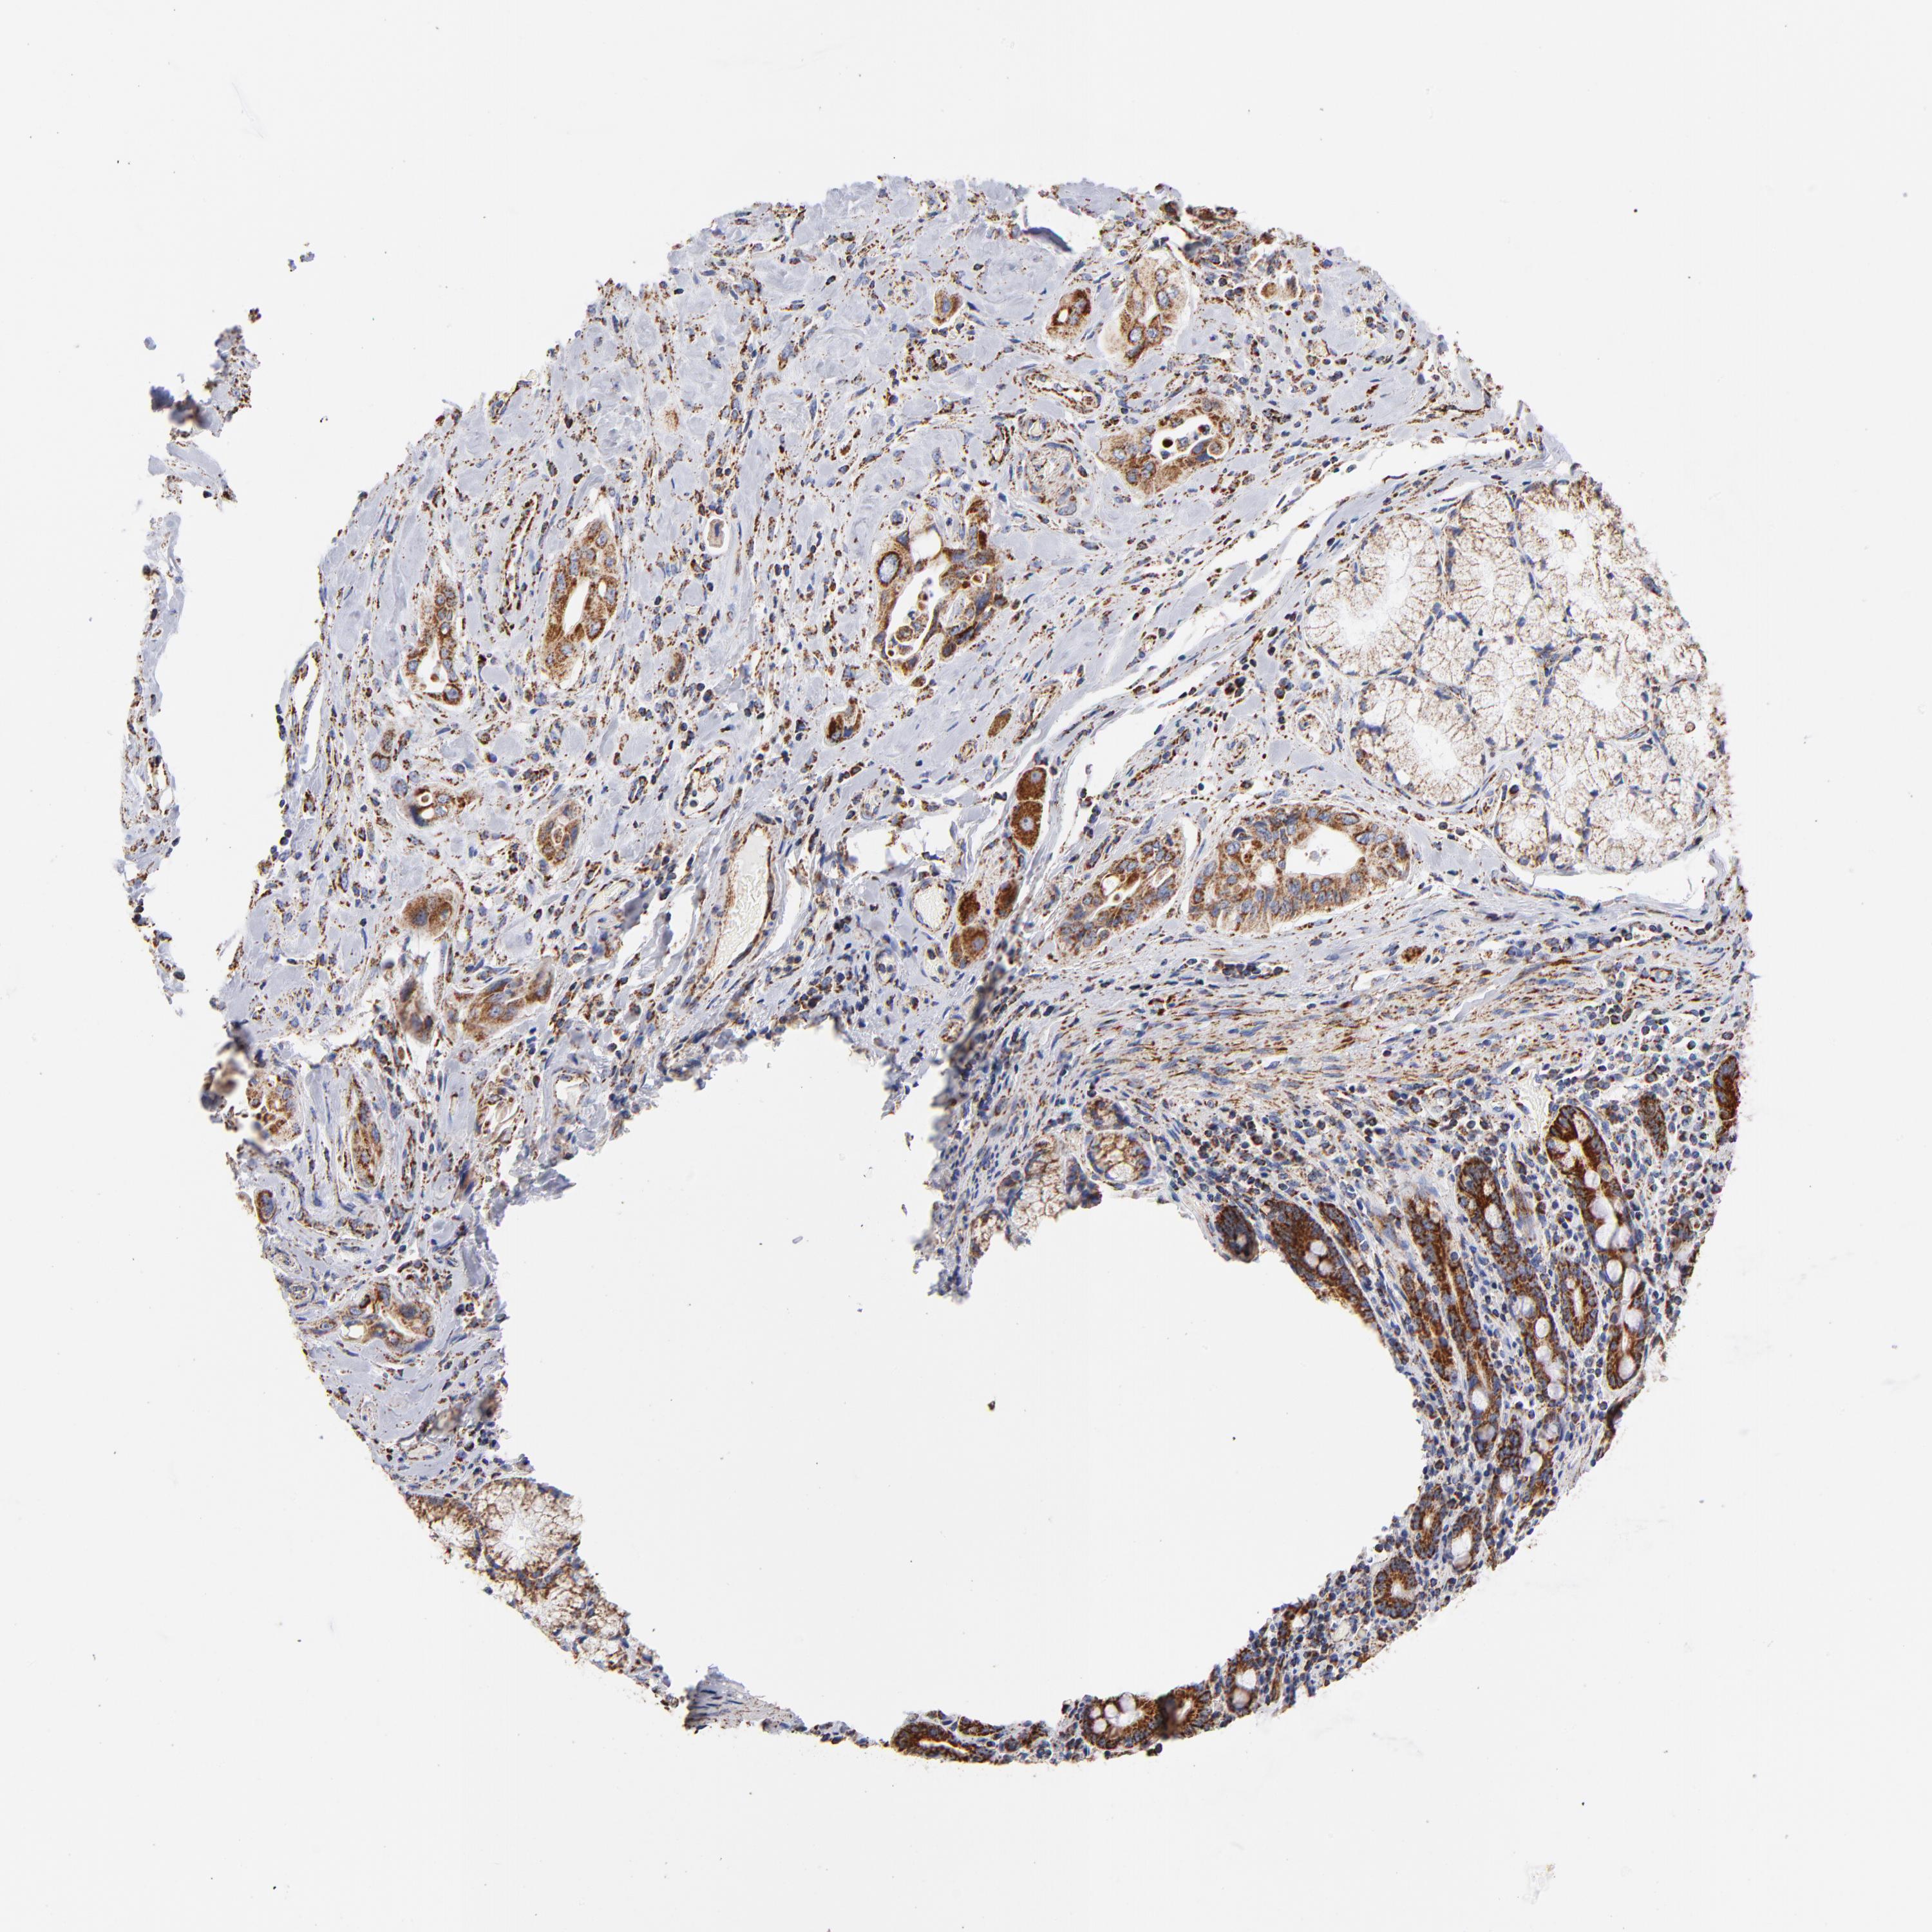

PANCREATIC CANCER - Protein expressioni

A mouse-over function shows sample information and annotation data. Click on an image to view it in a full screen mode. Samples can be filtered based on level of antibody staining by selecting one or several of the following categories: high, medium, low and not detected. The assay and annotation is described here.

Note that samples used for immunohistochemistry by the Human Protein Atlas do not correspond to samples in the TCGA dataset.

Antibody stainingi

Antibody staining in the annotated cell types in the current human tissue is reported as not detected, low, medium, or high, based on conventional immunohistochemistry profiling in selected tissues. This score is based on the combination of the staining intensity and fraction of stained cells.

Each image is clickable and will lead to virtual microscopy that enables deeper exploration of all samples and also displays staining intensity scores, fraction scores and subcellular localization as well as patient and tissue information for each sample.

Antibody HPA003280

Staining

High

Medium

Low

Not detected

Intensity

Strong

Moderate

Weak

Negative

Quantity

>75%

75%-25%

<25%

None

Location

Nuclear

Cytoplasmic/membranous

Cytoplasmic/membranous,nuclear

Adenocarcinoma, NOS

Adenocarcinoma, metastatic, NOS